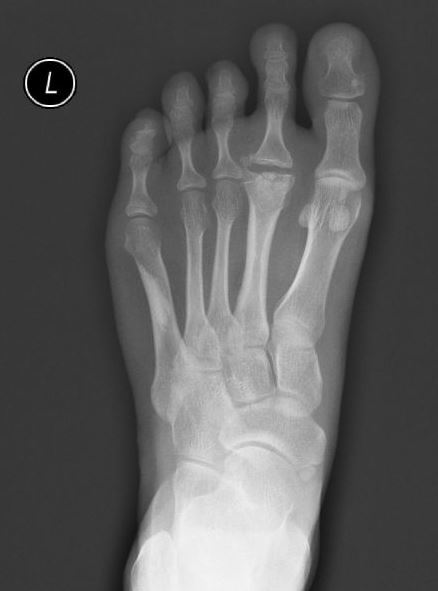

足部罕見(jiàn)病,特點(diǎn)是第2跖骨頭的骨質(zhì)破碎(偶有第3跖骨)最常見(jiàn)于年青女性,13-18歲通常無(wú)明顯癥狀,可外用止痛藥物或非甾體鎮(zhèn)痛藥(NSAIDs)持續(xù)疼痛,體育活動(dòng)受限,或骨質(zhì)增大穿鞋受擠壓時(shí),可考慮手術(shù)治療效果:通常采用截骨+經(jīng)皮克氏針/鈦針固定,明顯消除疼痛,改善功能并發(fā)癥:關(guān)節(jié)僵硬,轉(zhuǎn)移跖骨痛英文檢索Freiberg‘sDisease;Freiberginfractionhttps://www.ncbi.nlm.nih.gov/books/NBK537308/女:男約為4:1多見(jiàn)于青春期女性,13-18歲發(fā)??;多見(jiàn)于女性運(yùn)動(dòng)員解剖位置:第2跖骨,關(guān)節(jié)背側(cè),少見(jiàn)于第4、5跖骨風(fēng)險(xiǎn)因素:第2跖骨相對(duì)較長(zhǎng)的患者病因:外傷、過(guò)度應(yīng)力分期較早,或疼痛不明顯的,可考藥物鎮(zhèn)痛??诜悸宸?,或外用扶他林等。疼痛,腫脹嚴(yán)重,考慮手術(shù)治療。治療主要解決疼痛術(shù)前常規(guī)檢查通常是入院后抽血化驗(yàn)X線檢查:術(shù)前,術(shù)后,術(shù)后6周,術(shù)后1年門診復(fù)診:術(shù)后2周拆線,術(shù)后6周拔針體育活動(dòng):手術(shù)3個(gè)月后普通行走:術(shù)后6周開(kāi)始辦公、室內(nèi)活動(dòng):術(shù)后即刻